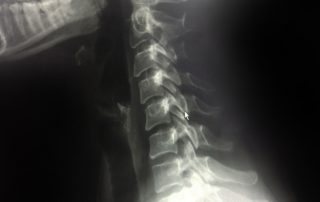

Omurga ameliyatı gerekliliği nasıl belirlenir? Hangi kriterler değerlendirilir? Cerrahi karar, hastanın şikâyetleri ve görüntüleme bulguları birlikte değerlendirilerek verilir. Cerrahi karar; hastanın şikâyetleri, görüntüleme bulguları ve yaşam kalitesi birlikte değerlendirilerek verilir. Omurga cerrahisi kararı, “MR’da bir şey var” diye verilmez. Aynı şekilde “çok ağrım var” diye de otomatik verilmez. Cerrahi karar, üçlü bir eşleşme ile netleşir: hastanın şikâyetleri + muayene bulguları + görüntüleme. Bunların üzerine dördüncü bir filtre daha eklenir: yaşam kalitesi. Çünkü omurga ameliyatının amacı, görüntüyü düzeltmek değil; sinir basısı gibi hedef problemi giderip hastanın işlevini geri kazandırmaktır. 1) Şikâyetin tipi: ağrının dili ne söylüyor? Cerrahi gerekliliği belirlemede ağrının karakteri [...]